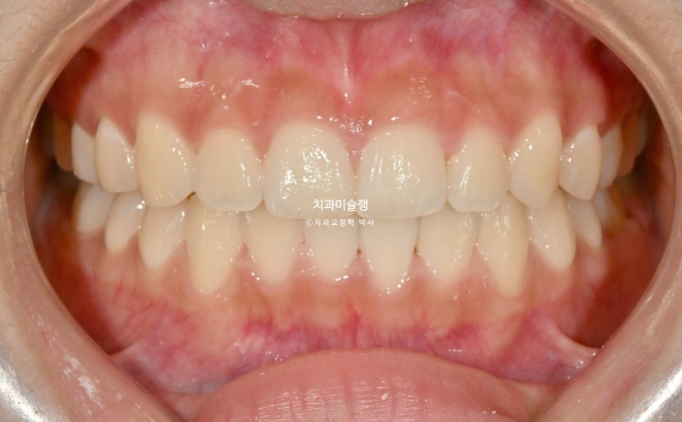

25.12

중심선은 맞아졌고

어금니 교합은 좌우 모두 1급 교합관계를 달성

이제 전 후 비교 보겠습니다.

총 치료기간은 1년 4개월 입니다.

24.07~25.12

해외에서도 장치를 잘 껴주어 결과가 좋습니다.